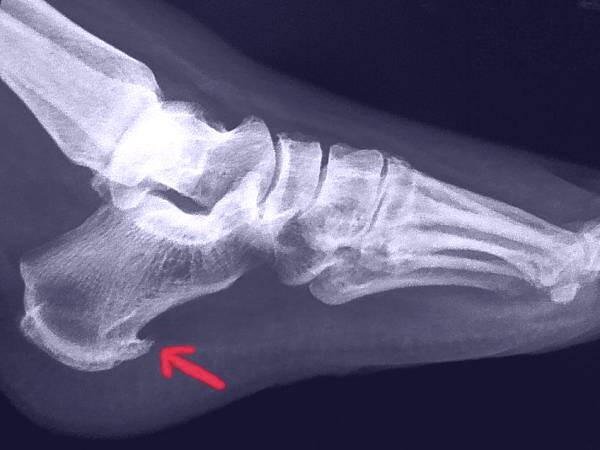

- پا (پاشنه)

چنانچه در ادامه این بخش از سلامت نمناک خواهیم گفت ممکن است متوجه نشوید که خار استخوانی دارید تا زمانی که اشعه ایکس پیدایش کند اما زمانی که بر روی اعصاب، تاندون ها و یا دیگر ساختارها در بدن خود فشار وارد کنند، مشکلاتی را ایجاد می کنند؛ سپس، ممکن است این احساس را پیدا کنید:

احتمالا ً باید به پزشک روماتولوژی یا ارتوپدی مراجعه کنید، روماتولوژیست متخصص مشکلات مفاصل هستند. پزشکان ارتوپد بر سیستم عضلانی اسکلتی تمرکز دارند می توانند توده خار استخوان را با لمس یا اشعه ایکس تشخیص دهند.